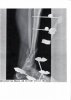

Wundheilung so gut wie abgeschlossen, nach erneutem Röntgen keine signifikante Kallusbildung,

Knochen also im Bruchzustand, wahrscheinlich wegen Antibiotika.